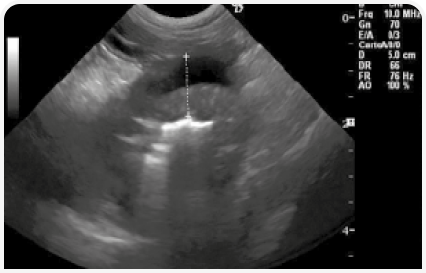

Биохимическое исследование крови, клинический анализ крови, анализ мочи, определение уровня панкреатической липазы, паразитологическое исследование фекалий и рентгенографическое исследование грудной клетки не выявили каких-либо нарушений, однако было отмечено значительное снижение уровня фолиевой кислоты и кобаламина (уровень фолиевой кислоты составлял 2,59 нг/мл (референсный интервал: 5–12), кобаламина < 150 нг/л (референсный интервал: 250–800)). При ультразвуковом исследовании было обнаружено выраженное утолщение стенки желудка при наличии местных реактивных изменений в мезентериальной жировой ткани (Рисунок 7).

По результатам исследования образцов стенки желудка, полученных методом тонкоигольной аспирационной биопсии под контролем ультразвука, было обнаружено нейтрофильное воспаление. С учетом серьезных подозрений на наличие неоплазии было проведено эндоскопическое исследование желудка. При этом патологических изменений пищевода, дна желудка и большой кривизны обнаружено не было, однако малая кривизна и антральный отдел характеризовались ригидностью и не поддавались расширению при инсуфляции; язвенных поражений не обнаружили. Тяжесть поражений привратника делала невозможным прохождение эндоскопа через пилорус (Рисунок 8).